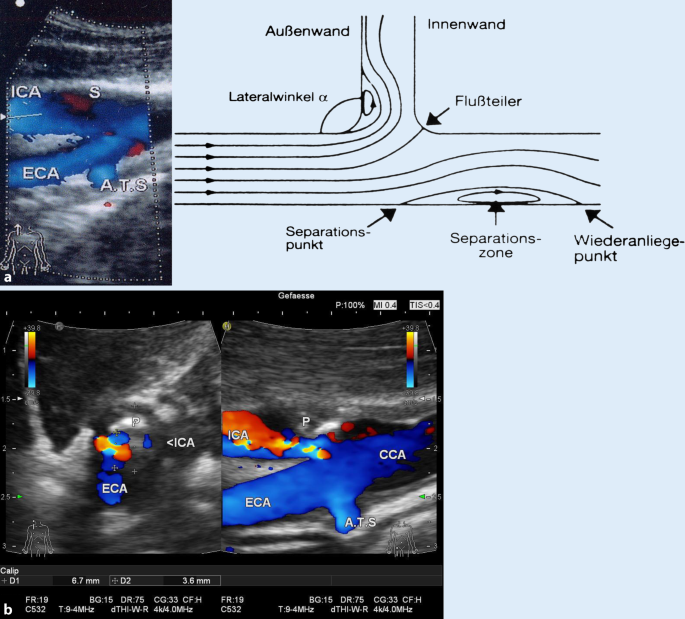

11 Carotid Artery Stenosis Part 1 B Mode And Color Flow 123 Sonography

Sonographische Graduierung Von Karotisstenosen Springerlink

Ultrasound Assessment Of Carotid Stenosis Radiology Key